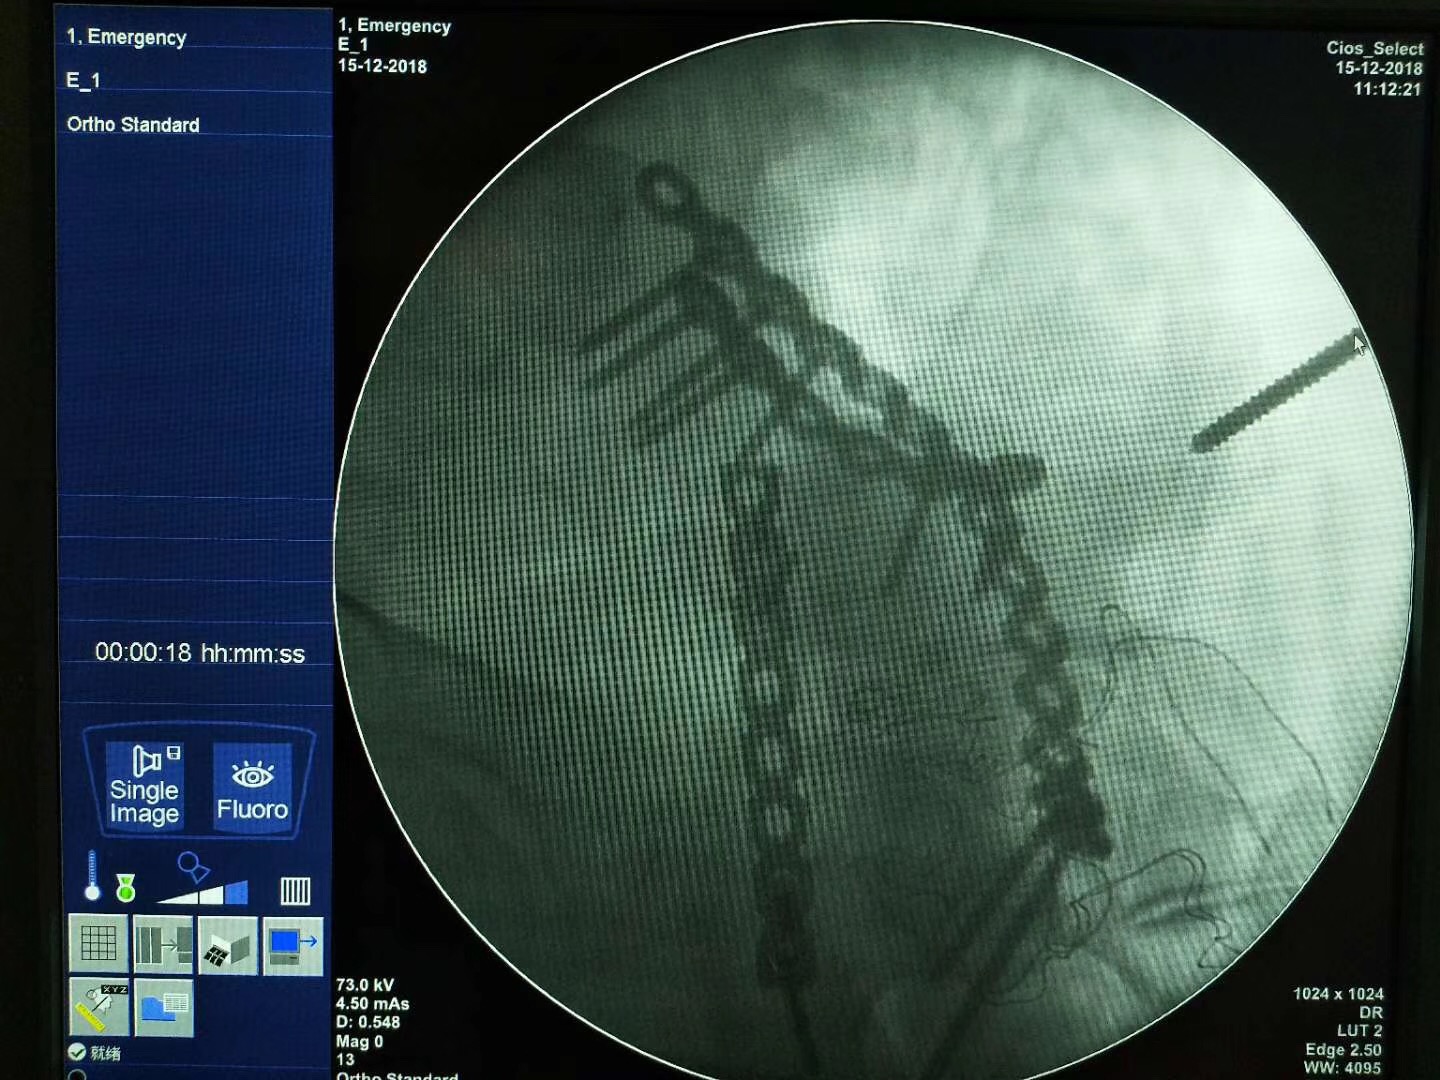

河南省安陽市人民醫院骨三科,接診一位52歲并患者,診斷為骨盆粉碎性骨折。我司收到影像數據后通過3D打印技術制作出3D打印病理模型,配合院方手術方案:切開復位內固定術。

術前模擬(匹配、預折彎)

\

術中應用

術中透視